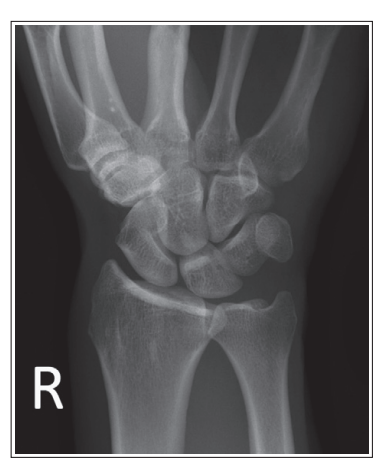

What is wrong with this oblique wrist xray

Under-rotated

Less than 45 degree obliquity